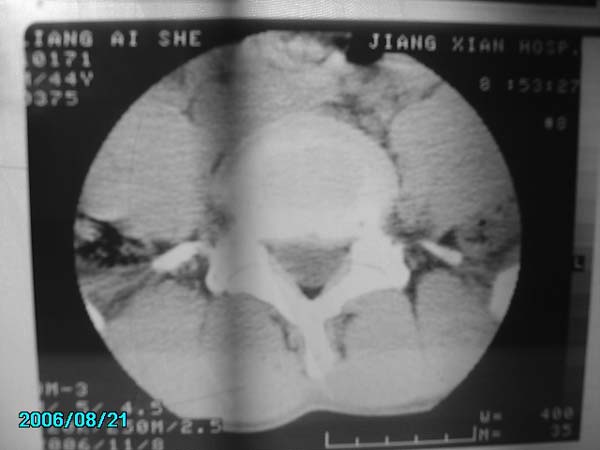

男,40岁,腰疼半年

腰4-5椎间盘后缘变平直,可考虑椎间盘轻度突出。余未见异常。

l4/5椎间盘膨出。

腰4-5椎间盘轻度突出。余未见异常。

腰椎侧弯,l4-5椎间盘膨出。

腰4-5、腰5-骶1椎间盘后缘变平直,可考虑椎间盘轻度突出。余未见异常